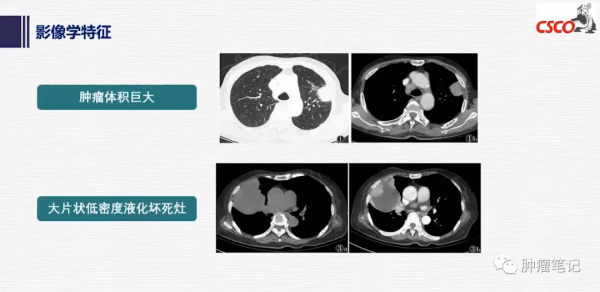

PSC在CT影像上具有一定特點,表現為腫瘤體積巨大;直徑多數>3cm,有的可達到18 cm;多為單發,中心型或外周型,圓形,密度均勻,邊緣光滑,可有毛刺或分葉,鈣化少見;增強CT呈環形或斑片狀強化;胸壁侵犯和(或)胸腔積液徵象。